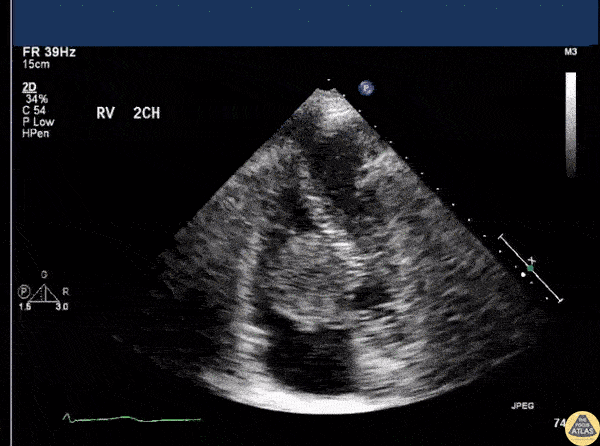

An apical 4 chamber view on a patient with CP, SOB, and palpitations revealed a right sided atrial myxoma. Image courtesy of Robert Jones DO, FACEP @RJonesSonoEM Director, Emergency Ultrasound; MetroHealth Medical Center; Professor, Case Western Reserve Medical School, Cleveland, OH View his original post here